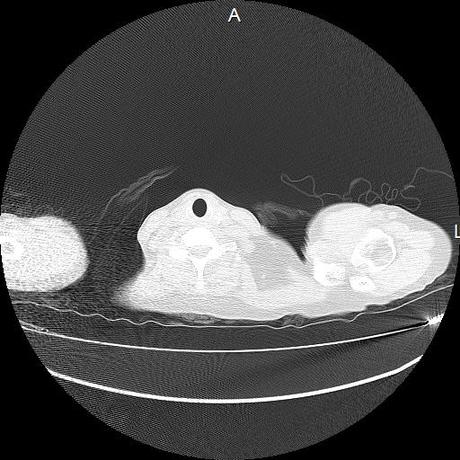

Se realiza volumen de tórax en fase simple, desde los opérculos torácicos hasta los hemidiafragmas, observándose:

Estructuras óseas sin evidencia de lesiones líticas, blásticas ni trazos de fractura. A nivel de cuerpo vertebral de T10 se observa nódulo de Schmorl que distorsiona el borde superior del cuerpo vertebral.

El parénquima pulmonar con areas parcheadas difusas en vidrio despulido combinadas con otras areas hipodensas de baja atenuación debidas a atrapamiento aéreo y engrosamiento intersticial y zonas de fibrosis de predominio en lóbulos medios e inferiores de ambos pulmones.